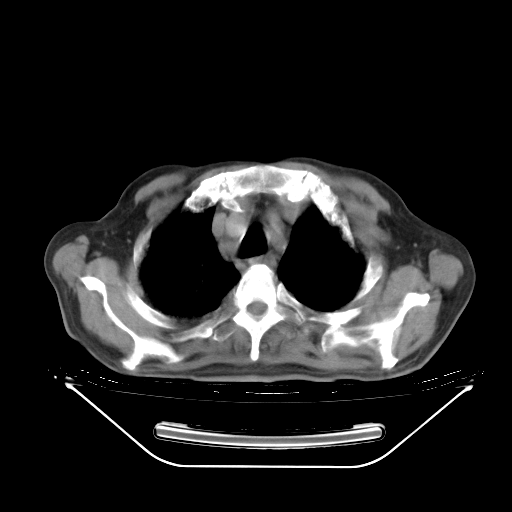

胸腹部CT,诊断意见:左上肺叶钙化灶、左侧胸膜局限性增厚并钙化、胆囊炎。描述部分肺组织呈磨玻璃样改变。

今天复查肺部CT,发现双肺广泛磨玻璃样改变。所以我把3月19日和5月9日相隔50天的肺部CT上传。请大家会诊。

2009年3月19日肺部CT片。

2009年3月19日肺部CT

大致读了系列胸部CT:纵隔窗无明显异常,肺窗:从4、27至今:主要是双肺中下野外带可见毛玻璃样改变,目前处于急性肺泡炎阶段,至于原因考虑1、结替组织或胶原血管性疾病所致?2、恶性疾病如恶组在肺部所致的表现或细支气管肺泡癌?3、药物或其它原因如肺蛋白沉着症所致肺泡炎目前不太可能?总之,明天就去请我院的呼吸科、感染科、血液科和临免专家会诊哈。